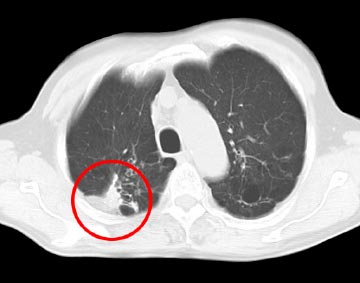

治療前のCT検査結果

治療前CTでは右肺の背面に原発性の肺がんと、その周囲のろっ骨浸潤が認められた。 この状況では手術による根治はほとんど期待できません。